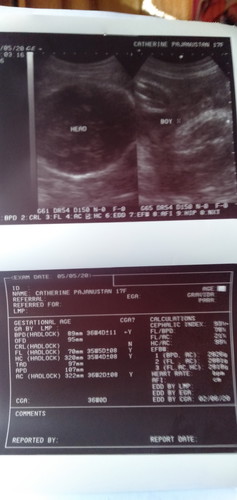

It's a boy ?

Hi baby boooy ? kala ni mama mo girl ka muntik ka na nya mabilhan ng gamit pang babae buti nalang sumagi sa isip ko na wag na muna ? hahaha Iloveyouuu kahit boy ka hinding hindi ako madidissappoint sayo ? tuwang tuwa papa mo kasw may mini me sya ?